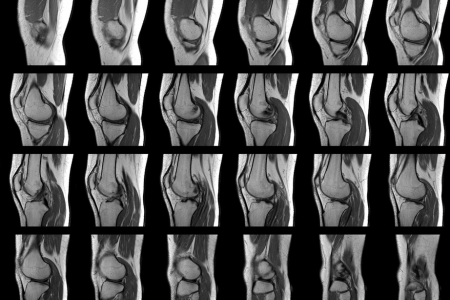

一方、MRI検査は、強力な磁石と電波を使って、体内の水分や脂肪などの情報を画像化する検査です。レントゲン検査とは異なり、骨だけでなく、軟骨、靭帯、筋肉、腱などの状態も詳しく調べることができます。レントゲンでは写らない軟骨の状態や、半月板(はんげつばん:膝関節にあるC型をした軟骨組織)の損傷なども、MRI検査では見つけることができます。

一方、MRI検査では、レントゲン検査では分からない、軟骨や靭帯、筋肉、腱などの状態まで詳しく分かります。軟骨のすり減り具合や、半月板の損傷、炎症の有無などを確認することができ、より詳細な診断が可能です。

変形性膝関節症の患者さんのMRIで非常によく見られるのが半月板の変性や損傷です。私の臨床経験では、これらの所見をどう解釈するかが治療方針の決定に大きく影響します。特に注目すべきは「横断裂(よこだんれつ)」と呼ばれる水平方向の断裂で、これは加齢や変性に伴って生じることが多く、必ずしも手術の対象にはなりません。

70代の女性患者さんは膝の痛みで来院し、MRIで内側半月板の横断裂が見つかりましたが、変形性膝関節症の所見も併せて認められました。この患者さんに対しては、半月板のみに注目した手術的アプローチではなく、変形性膝関節症の一環として保存的治療(非手術的治療)を選択したところ、症状は徐々に改善しました。

MRI検査では、骨だけでなく、軟骨や靭帯、半月板などの状態も詳しく調べることができます。半月板は、膝関節にあるクッションのような役割を果たす組織です。近年では、3テスラMRIのように、より鮮明な画像が得られる装置も登場し、より正確な診断が可能になっています。